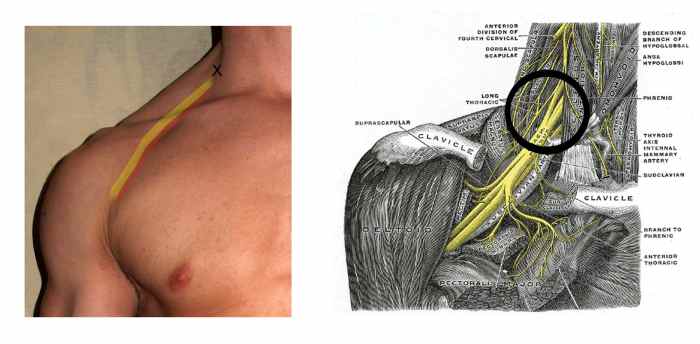

The X in the photo marks the site of injection for an interscalene block, while the diagram shows the target area.

By David Shankbone (Foto), Grey's anatomy. [GFDL (www.gnu.org/copyleft/fdl.html) or CC-BY-SA-3.0-2.5-2.0-1.0 (www.creativecommons.org/licenses/by-sa/3